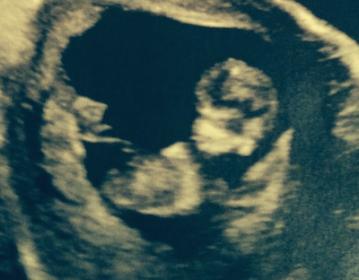

here is another

Boy!

If that is the nub then I am thinking boy. But it looks very early and baby is very curled up as well!

I'm guessing boy too :)

Definitely looks like a boy!

Boy